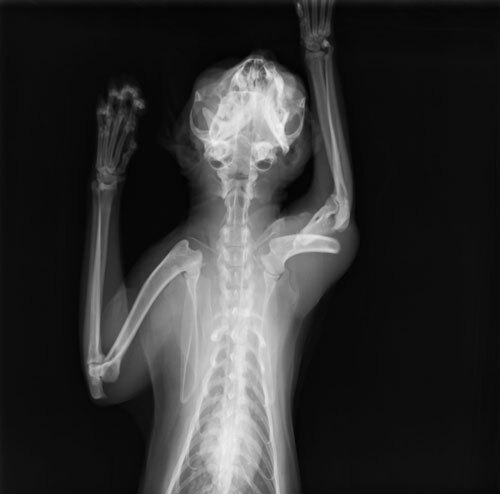

主題: 被人打斷腳的跛腳貓 申請者姓名: 陳世芬 花色: 申請日期: 2014-03-24 22:23:45 申請者部落格: https://www.facebook.com/fandy.chen 申請者臉書網址: http://blog.xuite.net/niblackcat/blog 所在縣市/合作醫院: 高雄市/銀星動物醫院 治療費用: 15200元 需求人數: 17人 已結案 (2014-05-18 09:39:47) 報名人員: 胖胖 x2(已付款)、屏東阿咩家(已付款)、機車寶(已付款)、JasmineC x2(已付款)、吳哆(已付款)、Lanny Shieh(已付款)、Chen Ping(已付款)、CHIU、yuki x3(已付款)、Ed Tsai(已付款)、lavinia x3(已付款)、思惟宗道(已付款)、 候補人員: 動物病情說明: 我在3/9救了一隻跛腳貓,是我餵養區域結紮的TNR貓咪,左前腳受傷,腳掌反折,三隻腳用跳的行動,疑似被人打斷腳,送至動物醫院,做了血檢和x光檢查,貓咪上半肢骨折,下半肢腳掌神經受損,目前有微弱反應。3/10和3/11看了五家醫院,醫生說貓咪還有機會可以把骨頭位置接回,可做骨頭重建手術,但神經受損部分需術後觀察才能知道,如果不做手術,姿勢不對,未來可能會腳拖地受傷,到時候就要截肢。

貓咪3/14在銀星動物醫院完成手術,3/24出院。